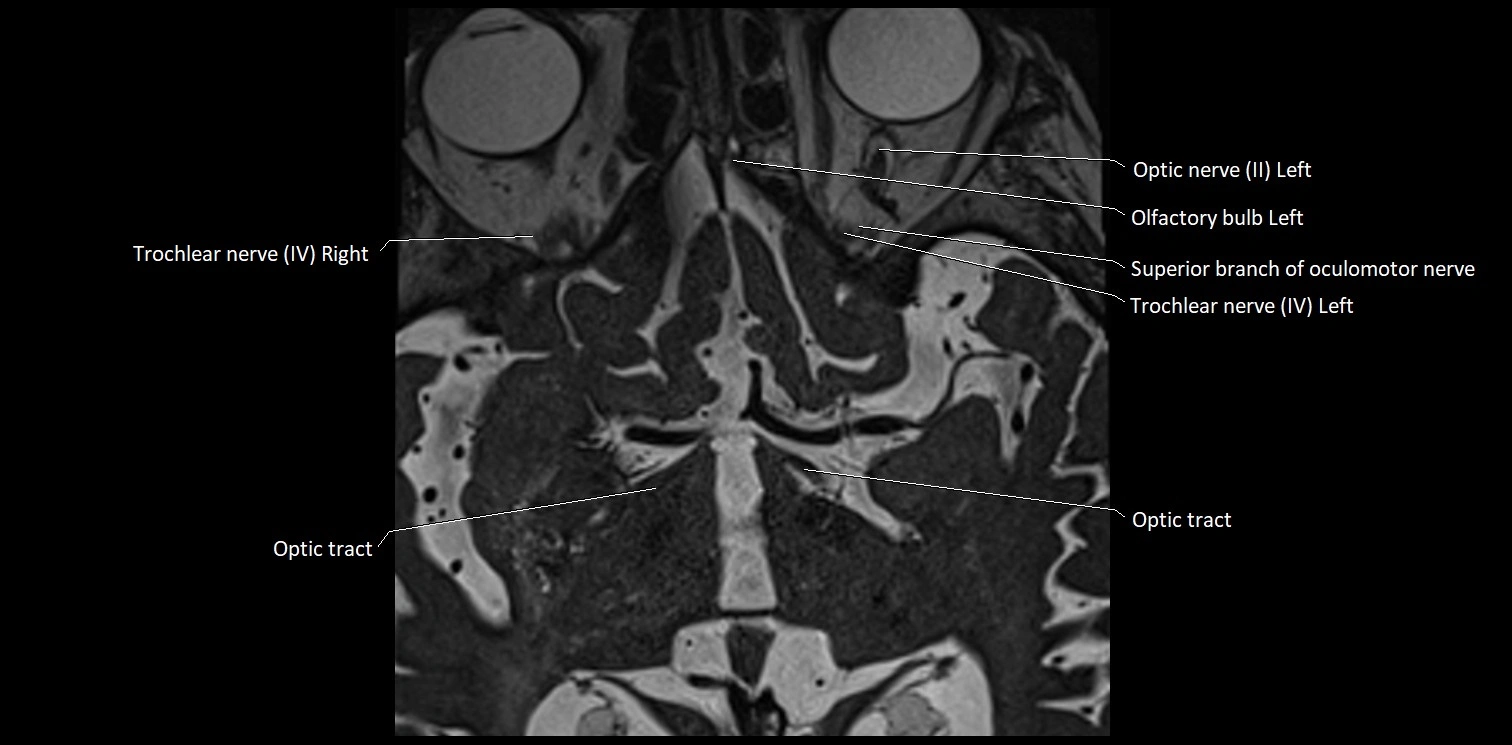

MRI Appearance

• The abducens nerve is a small, thin, linear structure

• Best visualized on high-resolution T2-weighted 3D MRI sequences (e.g., FIESTA or CISS)

• Seen as a hypointense (dark) line running from the brainstem at the pontomedullary junction, traversing the prepontine cistern, and entering Dorello’s canal under the petrosphenoidal ligament, then into the cavernous sinus, and finally the orbit

• May be challenging to visualize in standard MRI due to its small size

• Pathology may be inferred by absence, displacement, or enhancement of the nerve